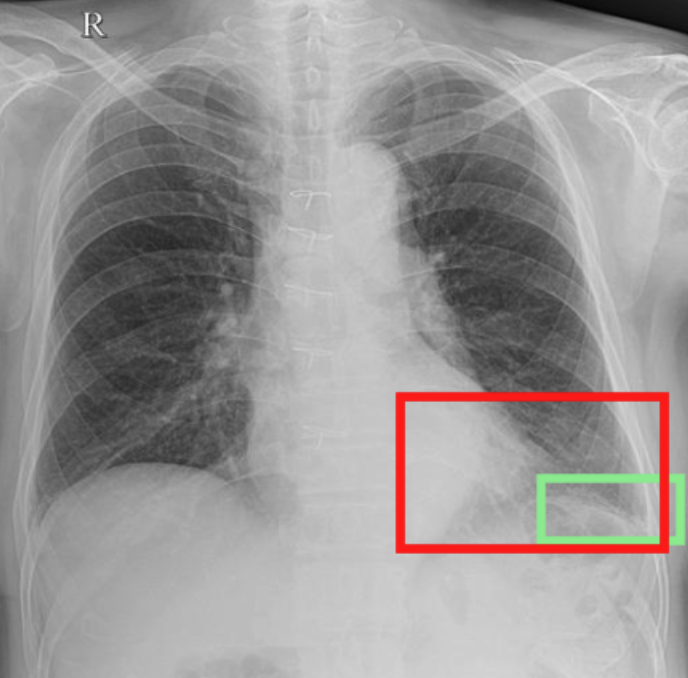

4.3.3 Visual grounding

In this section, we evaluate RadVLM’s visual grounding capabilities, which could help clinicians localize specific regions or pathologies on a CXR. This is particularly useful once a pathology has already been identified – either by a radiologist’s input or through our previously described AI tasks – since it allows one to pinpoint exactly where the abnormality appears on the image.

We report performance metrics for the three main grounding tasks RadVLM was trained on: anatomical grounding using the Chest Imagenome test set, abnormality grounding using the VinDr-CXR test set, and phrase grounding using the MS-CXR test set (Table 1). For each task, we use mean Average Precision (mAP) as our primary evaluation metric.

As mentioned in Table 2, some of the CXR-specific VLMs already have grounding capabilities. CheXagent was trained to handle both abnormality and phrase grounding tasks, while MAIRA-2 – originally trained to produce radiology reports with grounded observations – is also capable of predicting bounding box coordinates when provided with input text. After retrieving each model’s instruction template for generating bounding box coordinates (Appendix 1-Table 2), we evaluated both CheXagent and MAIRA-2 on all three grounding tasks performed by RadVLM.

Our results show that RadVLM performs well at localizing anatomical regions (e.g., “right lung”, “aortic arch”, illustrated in Figure 5a), achieving a mAP of 85.8 %, by far surpassing the other CXR grounding models (Table 4). This advantage is partly explained by including the Chest Imagenome dataset (and thus the anatomical grounding task) in the training set, which CheXagent and MAIRA-2 did not leverage. However, it remains a key feature for any grounding model to possess a fine-grained understanding of CXR anatomy.

For the abnormality grounding task, RadVLM is less consistent (Figure 5b), likely due to higher sparsity of abnormality locations and labels, yet it still achieves best performance (Table 4). For the phrase grounding task, while MAIRA-2 and CheXagent demonstrate great performance, RadVLM surpasses them with a mAP of 81.8% (Table 4), presumably benefiting from the newly released PadChest-GR dataset (Castro et al.,, 2024) used for training.

Overall, these results show that our instruction tuning strategy for visual grounding (covering three essential tasks), combined to a modern VLM backbone, offers a promising avenue to help clinicians localize anatomical and pathological features during a CXR exam. Furthermore, providing fine-grained details within an LLM-generated output may also enhance the ability to answer grounded questions in a multi-turn setting, as we explore next.

a. Anatomical grounding

silhouette

junction

structures

lung

abdomen

mediastinum

arch

b. Abnormality grounding

thickening

fibrosis

enlargement

lung disease

| Anatomical grounding | Abnormality grounding | Phrase grounding | |

| CheXagent | 6.2 | 26.0 | 69.7 |

| MAIRA-2 | 19.8 | 11.3 | 80.1 |

| RadVLM | 85.8 | 34.6 | 81.8 |